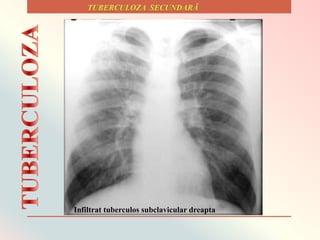

Tipuri de infiltrate tuberculoase secundare.

Infiltrat tuberculos subclavicular dreapta